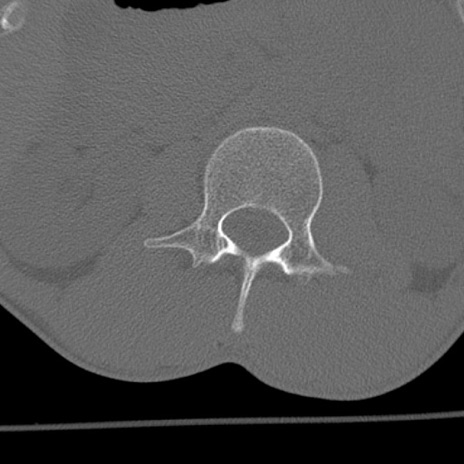

症例3 腰椎CT(横断像)

腰椎CT